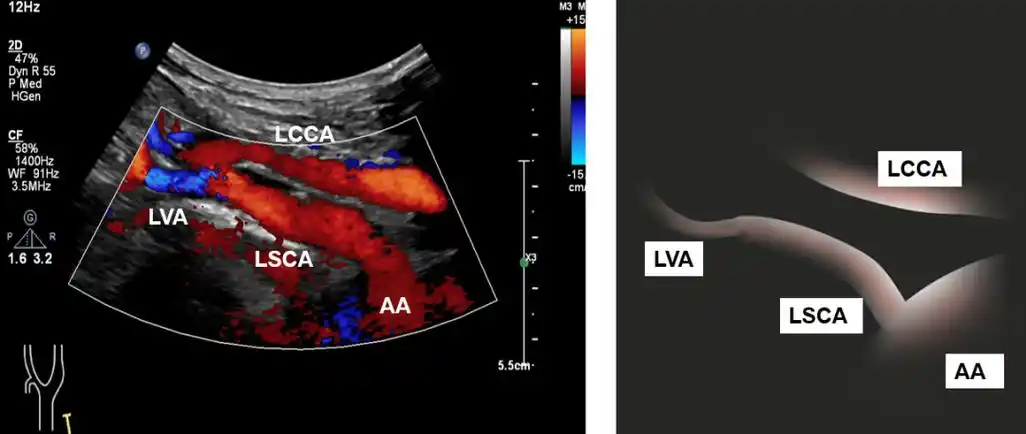

锁骨下动脉窃血综合征超声诊断图解

锁骨上的锁骨下动脉

锁骨下动脉的超声扫查——解剖,分段,扫查方法与标准切面

锁骨下动脉的超声检查——推荐扫查流程及常见病变的评估

超声检查对于右锁骨下动脉及颈总动脉显示较易,而无名动脉及左锁骨下

超声新手福利:锁骨下动脉盗血综合征